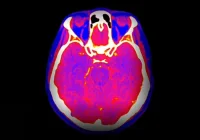

Photon-counting CT has introduced a paradigm shift in vascular imaging, employing advanced photon detectors for superior image resolution. Unlike conventional CT scanners, which integrate energy across photons, PCCT detects individual photons and distinguishes between their energy levels. This technology significantly reduces image noise and enhances spatial resolution, enabling detailed visualisation of vascular structures.

These improvements are particularly advantageous in PAD diagnosis. One of the longstanding challenges in vascular imaging has been differentiating between intravascular contrast and calcified plaques. Traditional CT angiography often struggles in this area, leading to overestimating stenosis or false-positive results. This is especially problematic in the calf arteries, where smaller vessel diameters and dense calcifications exacerbate diagnostic difficulties. Photon-counting CT addresses this limitation by minimising artefacts such as blooming—an effect where calcifications appear larger than they are—thus improving diagnostic precision. Additionally, PCCT enhances the iodine signal in contrast imaging, facilitating clearer delineation of stenotic lesions even in small and calcified vessels.